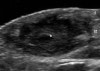

다른 종양과의 감별진단을 위해 초음파를 적용할 수 있습니다.

초음파 : 손의 표피 낭종(Epidermal cyst in the hand)